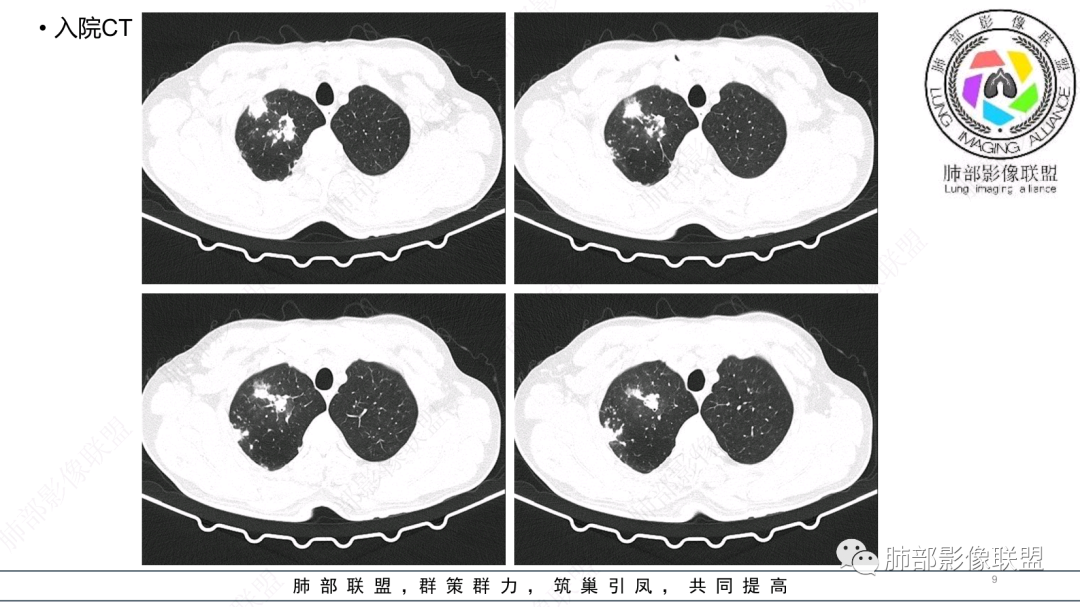

中老年男性,发病一周,发热,炎症指标明显增高,双肺支气管扩张基础,双肺可见多发结节、斑片状、团块状密度增高,边缘尚清。病灶分布与支气管关系密切,考虑支扩合并感染,铜绿,NTM、奴卡、曲霉等,环卫工人,可能接触腐败物较多,考虑曲霉可能大,鉴别奴卡。

中老年男性,发病一周,发热,炎性指标高,职业环卫工人,两肺弥漫分布肉芽肿结节病变,以胸膜下及支气管血管束分布为主,两肺多发支气管扩张,奴卡,结核,曲霉。

男性,56岁,清洁工,临床表现咳嗽咳痰发热。胸部影像:两肺散在斑片、结节及实变影,大部分沿气道分布,以下肺为著并伴发多发支气管扩张及囊腔影,实验室检查白细胞增高,考虑感染性病变,曲霉、铜绿及NTM。

两肺支扩,两肺沿支气管分布多发结节、树芽及团块,边缘模糊,部分支气管管壁增厚,考虑气道侵袭性曲霉菌,鉴别铜绿、奴卡、结核。

CT:双肺延支气管血管束分布斑片状、团块状、树芽状密度增高影,部分边界模糊,支气管扩张、部分管壁增厚。考虑气道吸入细菌性感染,铜绿假单孢?